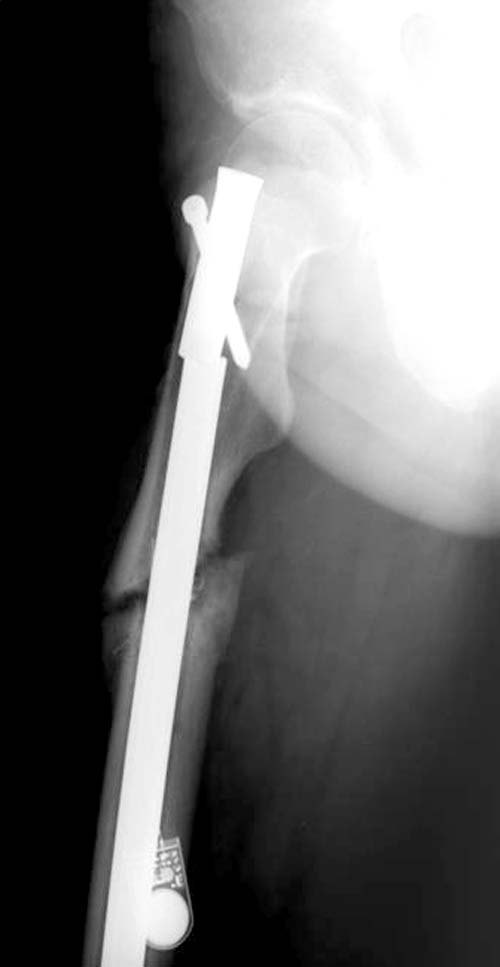

Имя     : 1 Fem nonunion ap-1.jpg

Тип     : image/jpg

Размер  : 26866 байтов

Описание: отсутствует

Url     : http://weborto.net:8080/pipermail/ortho/attachments/20111214/0c6bb1fc/attachment-0004.jpg

Нестабильность не только дистальных винтов, а также всей конструкции, которая свободно плавает внутри канала. Болтающийся штифт, сильные боли при ходьбе, а также отсутствие консолидации напоминает клиническую картину инфекцию канала. При подтверждении инфицированного ложного сустава лабораторно или клиническими исследованиями дальше по протоколу: промывание и риминг, временнный спейсер с антибиотиком и окончательная фиксация после разрешения процесса.

Перештифтовать на более толстый стержень - обычная тактика при асептических ложных суставах, и для стимуляции процесса необходимо дополнительный риминг канала не менее 2 мм больше, чем диамер гвоздя. Но в данном случае риминг канала надо больше чем обычно, до здорового кортекса, т.е. получается больше, чем два мм!

Для большинства свежих переломов достаточным бывает стандартный Gamma 3 с диаметром в 10 и 11 мм, но для реконструкции, тем более с большим диаметром канала обычный гвоздь немного тонковат. Чем плотнее, тем лучше, и Страйкер производит Long Gamma гвозди, не знаю как у вас, но у нас гвозди с большим диаметром надо заказывать заранее.